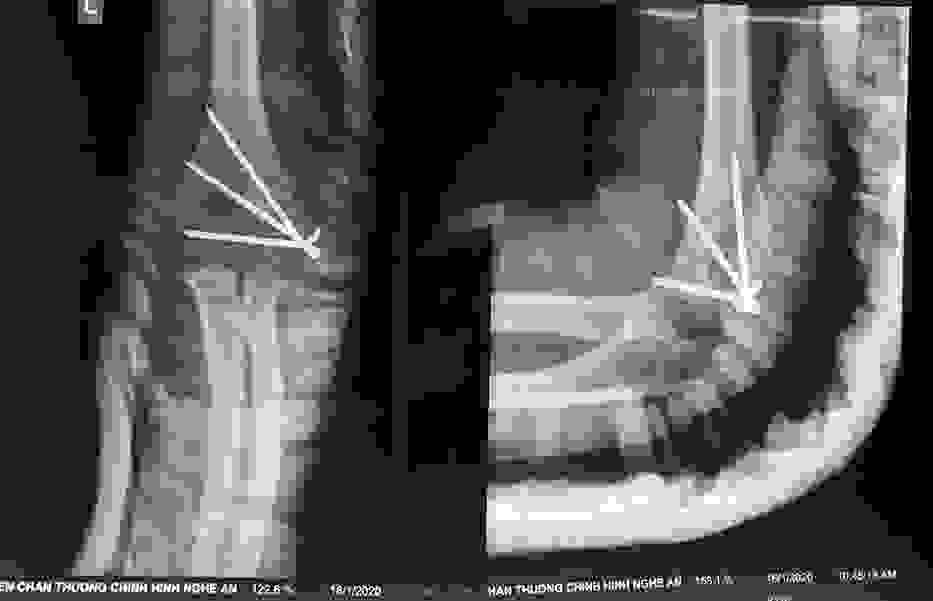

Phẫu thuật thành công ca bệnh hiếm gặp...khớp giả bẩm sinh xương chày

26/06/2019 17:00

Đã xem: 3330

Bệnh viện Chấn thương- Chỉnh hình Nghệ An, vừa phẫu thuật thành công cho bệnh nhi khớp giả bẩm sinh xương chày